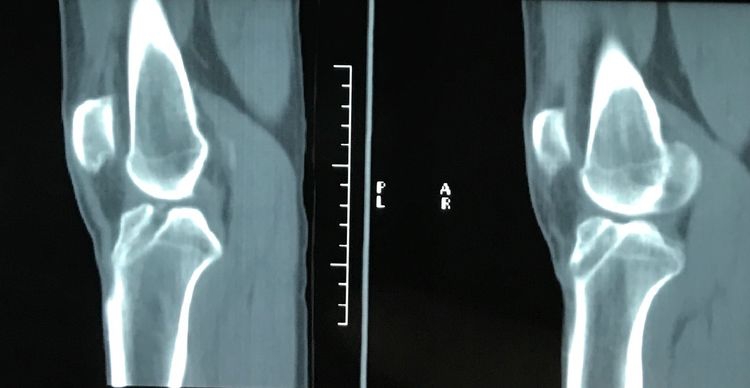

CT检查显示ACL重建的胫骨隧道偏前,股骨隧道偏后。

为了更加清晰明了,尝试使用3D打印技术帮助进行ACL返修手术,3D打印可以清楚显示原来重建的隧道内口及外口等等诸多情况,还可以探究ACL重建失效的原因、下一步的手术处理等等。